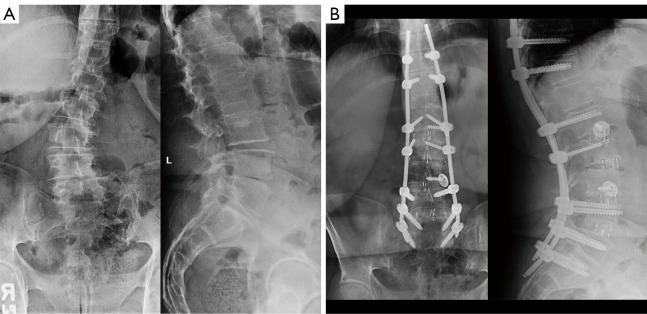

Abstract Image